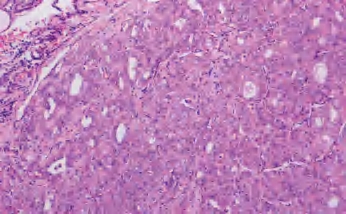

(1)滤泡亚型:由小至中等大小、不规则滤泡形成,实际上不含乳头结构,滤泡内含胶质,构成滤泡的上皮细胞有大而亮的核,含核沟和核内假包涵体。大约1/3此类肿瘤有包膜,预后与通常的乳头状癌相似(图3-44、图3-45)。

图3-44 甲状腺乳头状癌,滤泡亚型

图3-45 甲状腺乳头状癌,滤泡亚型